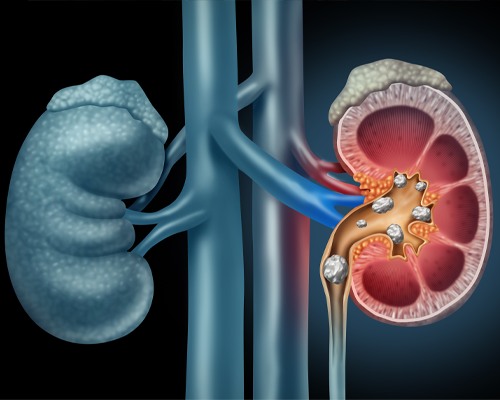

Kidney stone disease is a common urological condition in which hard mineral deposits form in the kidneys or urinary tract. These stones can cause severe pain, urinary obstruction, recurrent infections, and may lead to kidney damage if not treated on time.